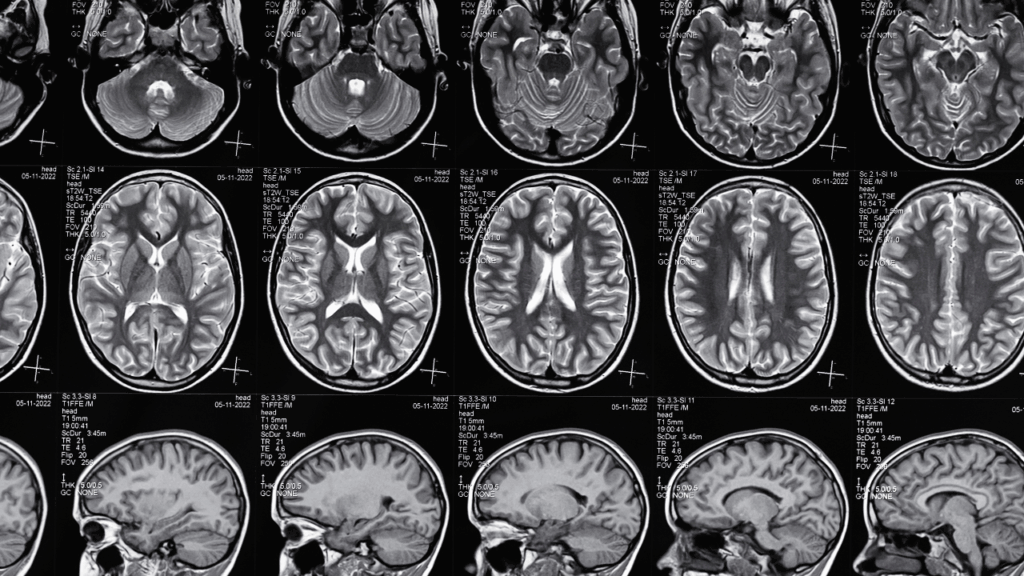

Traumatic brain injuries (TBIs) are among the most devastating outcomes of accidents. Unlike broken bones, which can heal over time, brain injuries often create lasting physical, emotional, and financial challenges. Victims may struggle with memory loss, difficulty concentrating, mood changes, or even the inability to work or live independently.

Brain injuries aren’t always visible, making them harder to diagnose and prove in court. Victims may experience:

Brain scans may not always capture the full impact of a TBI. Attorneys must rely on medical experts, neuropsychologists, and testimony from family members to show how the injury changed the victim’s life.